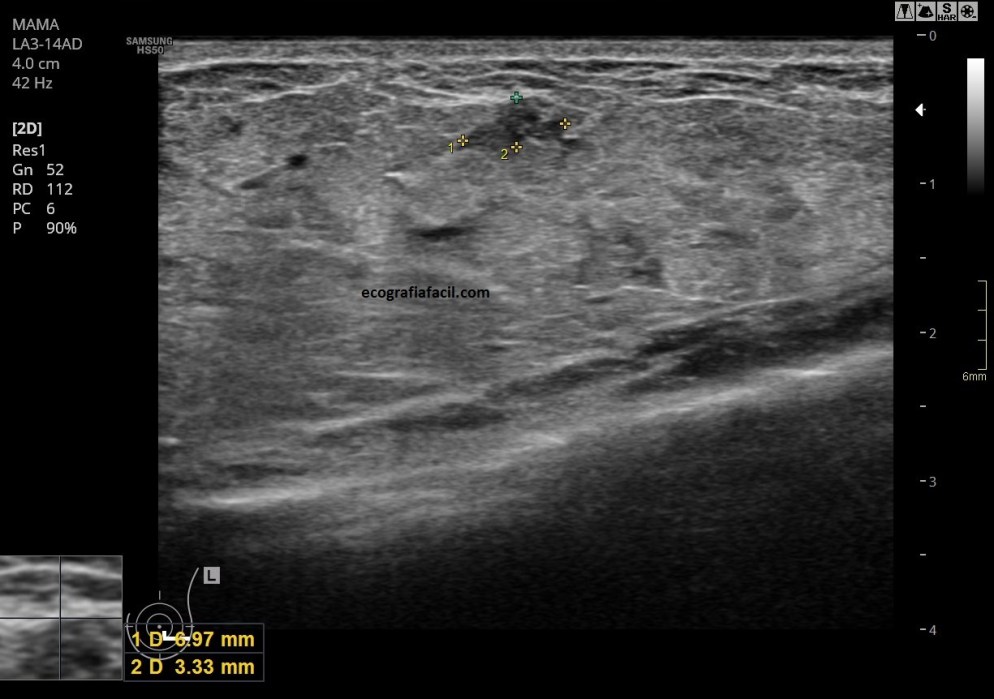

En la imagen 3 y 4 vemos una imagen clarificadora de lo que es una ecografía de mama «normal» y la misma imagen meses después cuando la mama está en proceso de lactancia.

Lo que vemos semiológicamente comparando imagen 3 y 4, es una estructura aumentada de tamaño, más abigarrada y donde observamos que el tejido glandular está aumentadísimo, aumentado también en su hiperfrefringencia, incluso, la lesión que se observa en la imagen 3 se ve como difuminada en la imagen 4…todos esos cambios que se observan claramente en la última imagen.

Conductos dilatados, anecoicos, distribuidos por todo el tejido hiperecogénico típico de esta situación de la lactancia.

In images 3 and 4 we see a clarifying image of what is a «normal» breast ultrasound and the same image months later when the breast is in the process of breastfeeding.

What we see semiologically comparing images 3 and 4, is an enlarged structure, more variegated and where we observe that the glandular tissue is greatly increased, also increased in its hyperfrequency, even, the lesion seen in image 3 is seen as blurred in image 4 … all those changes that are clearly observed in the last image.

Dilated, anechoic ducts, distributed throughout the hyperechogenic tissue typical of this situation of lactation.